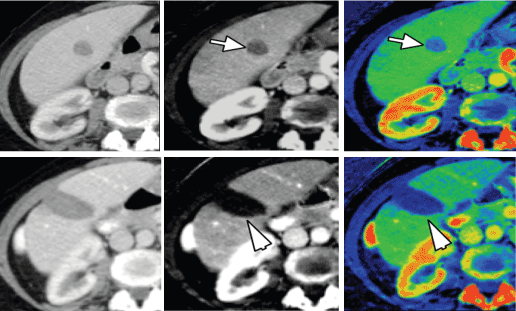

DECT has several applications in every initial and post-treatment medicine imaging. By increasing lesion eminence, growth margins square measure higher printed, thus, property accuracy in measurement of the scale of lesions (Figure 5) [5].

Figure 5. A. 72-year-old man with a history of jaundice treated with biliary tube placement. (A) Single-energy CT pictures, that place confidence in variations in Hounsfield units, show degree ill-defined area of heterogeneous improvement among the uncinate methodology of the secretor (arrow). (B) Iodine material decomposition pictures (GE), that demonstrate the actual uptake or concentration of iodine in tissues, facilitate to higher characterize and describe the extent of this hypo enhancing mass (arrow), compatible with ductal carcinoma. to boot note but the whole reduction in twin energy CT results in a higher image of the metal tube containing refluxed oral contrast media.

Accuracy in a measure is extremely necessary for guiding management, notably for patients in clinical trials throughout that growth response is looking forward to serial measurements per the various criteria for analysis of tumors [21,22]. due to the potential ability of quantitative iodine maps for the analysis and quantification of the viability of neoplasm, DECT has an extra potential for assessment of the response to treatment twenty-one [22]. this is often a rousing development that permits for characterization of neoplasm at a purposeful level that anticipates any modification in size [21], though this technique wants validation and standardization. to boot to increasing lesion eminence, low Kev and material density pictures can also offer correct image of regional extent of malady and relationships to adjacent vasculature that's helpful to guide treatment prepare [22]. curiously, iodine maps can facilitate in differentiating a neoplasm from bland coagulum through qualitative and quantitative demonstration of iodine among the clot. This differentiation is diagnostic in staging hepatocellular and internal organ malignant neoplastic disease [22]. DECT can facilitate in assessing the response to treatment involving therapies targeted to express regions, such as ablation (e.g., radiofrequency, microwave, cryo), targeted irradiation (e.g., protons), and intra-arterial medical aid (e.g., selective internal irradiation [SIRT] and transarterial chemoembolization [TACE]) [23,21,22]. Iodine maps obtained sort of a shot once radiofrequency ablation has shown higher lesion conspicuity and internal homogeneity of the ablation zone, providing an additional profit for assessing the security once radiofrequency ablation. In our observations, we've observed that iodine pictures are helpful not only sort of a shot once the procedure but to boot for following from patients undergoing internal organ microwave/radiofrequency ablation and internal organ cryo/radiofrequency ablation (Figure 6).

Figure 6. A 62-year-old girl with a history of a malignant neoplastic disease and a solitary liver metastasis. (A) Single energy CT image learned at a hundred and forty kVp, (B) material decomposition iodine image, and (C) color overlay iodine image demonstrate the solitary heterogeneous liver lesion in part V. Material decomposition iodine pictures (B, C) demonstrate moderate uptake of iodine (arrows), suspicious for metastasis, that was later confirmed at assay. Following radiofrequency ablation, the 140kVp pictures(D) still show heterogeneous attenuation among the metastasis, raising suspicion for incomplete ablation or repetition. However, iodine pictures (E, F) show no uptake of iodine (arrowheads), excluding recurrence/ incomplete ablation; the heterogeneous look of the lesion is maybe going due to post-treatment trauma.